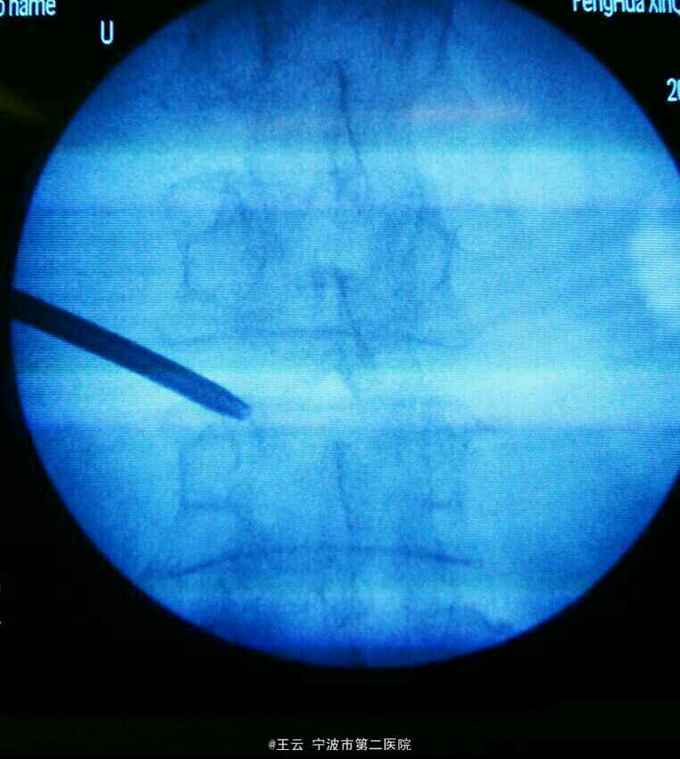

诊断:L3/4椎间盘脱出 治疗:经椎间孔入路椎间孔镜下髓核摘除,射频消融